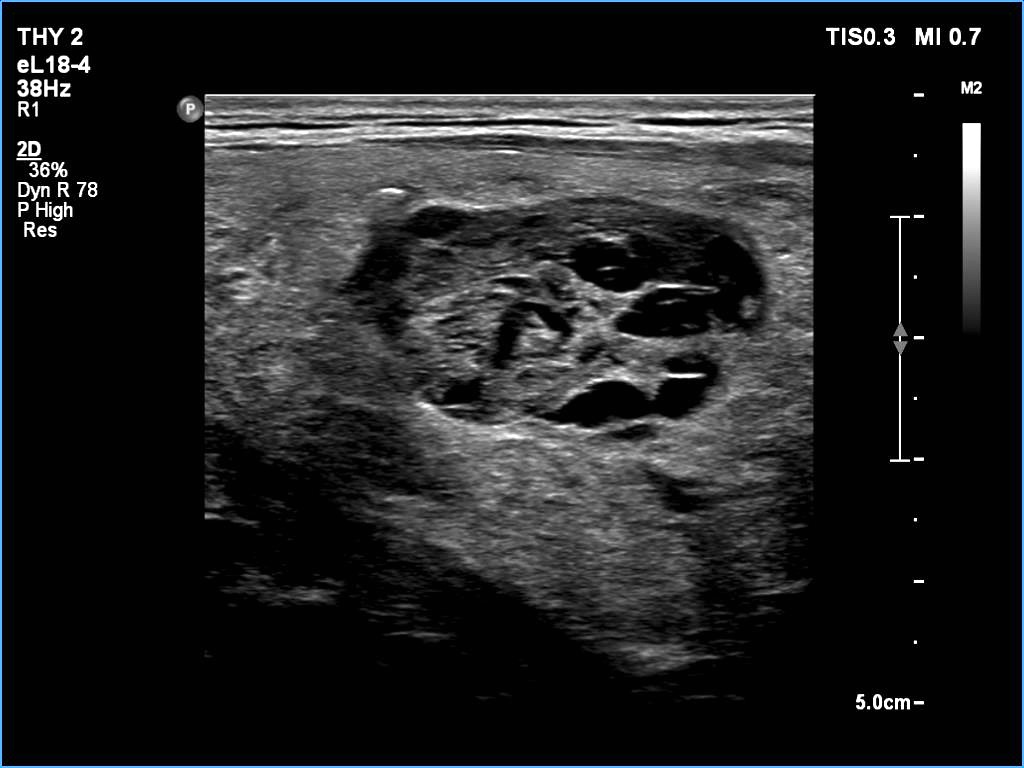

Ultrasonography: The thyroid was echonormal. There was a larger nodular mass in the right lobe which was composed of a dominantly solid echonormal portion that surrounded a dominantly cystic area. There were multiple nodules in the left lobe. The latter included an almost completely cystic lesion.

Comment. The right nodule is dominantly solid one because the cystic portion is less than 50%. The cystic portion of the nodule is multichambered which presents spongiform areas. The left cystic nodule is an almost completely cystic lesion, that has disappeared after the removal of cystic fluid.